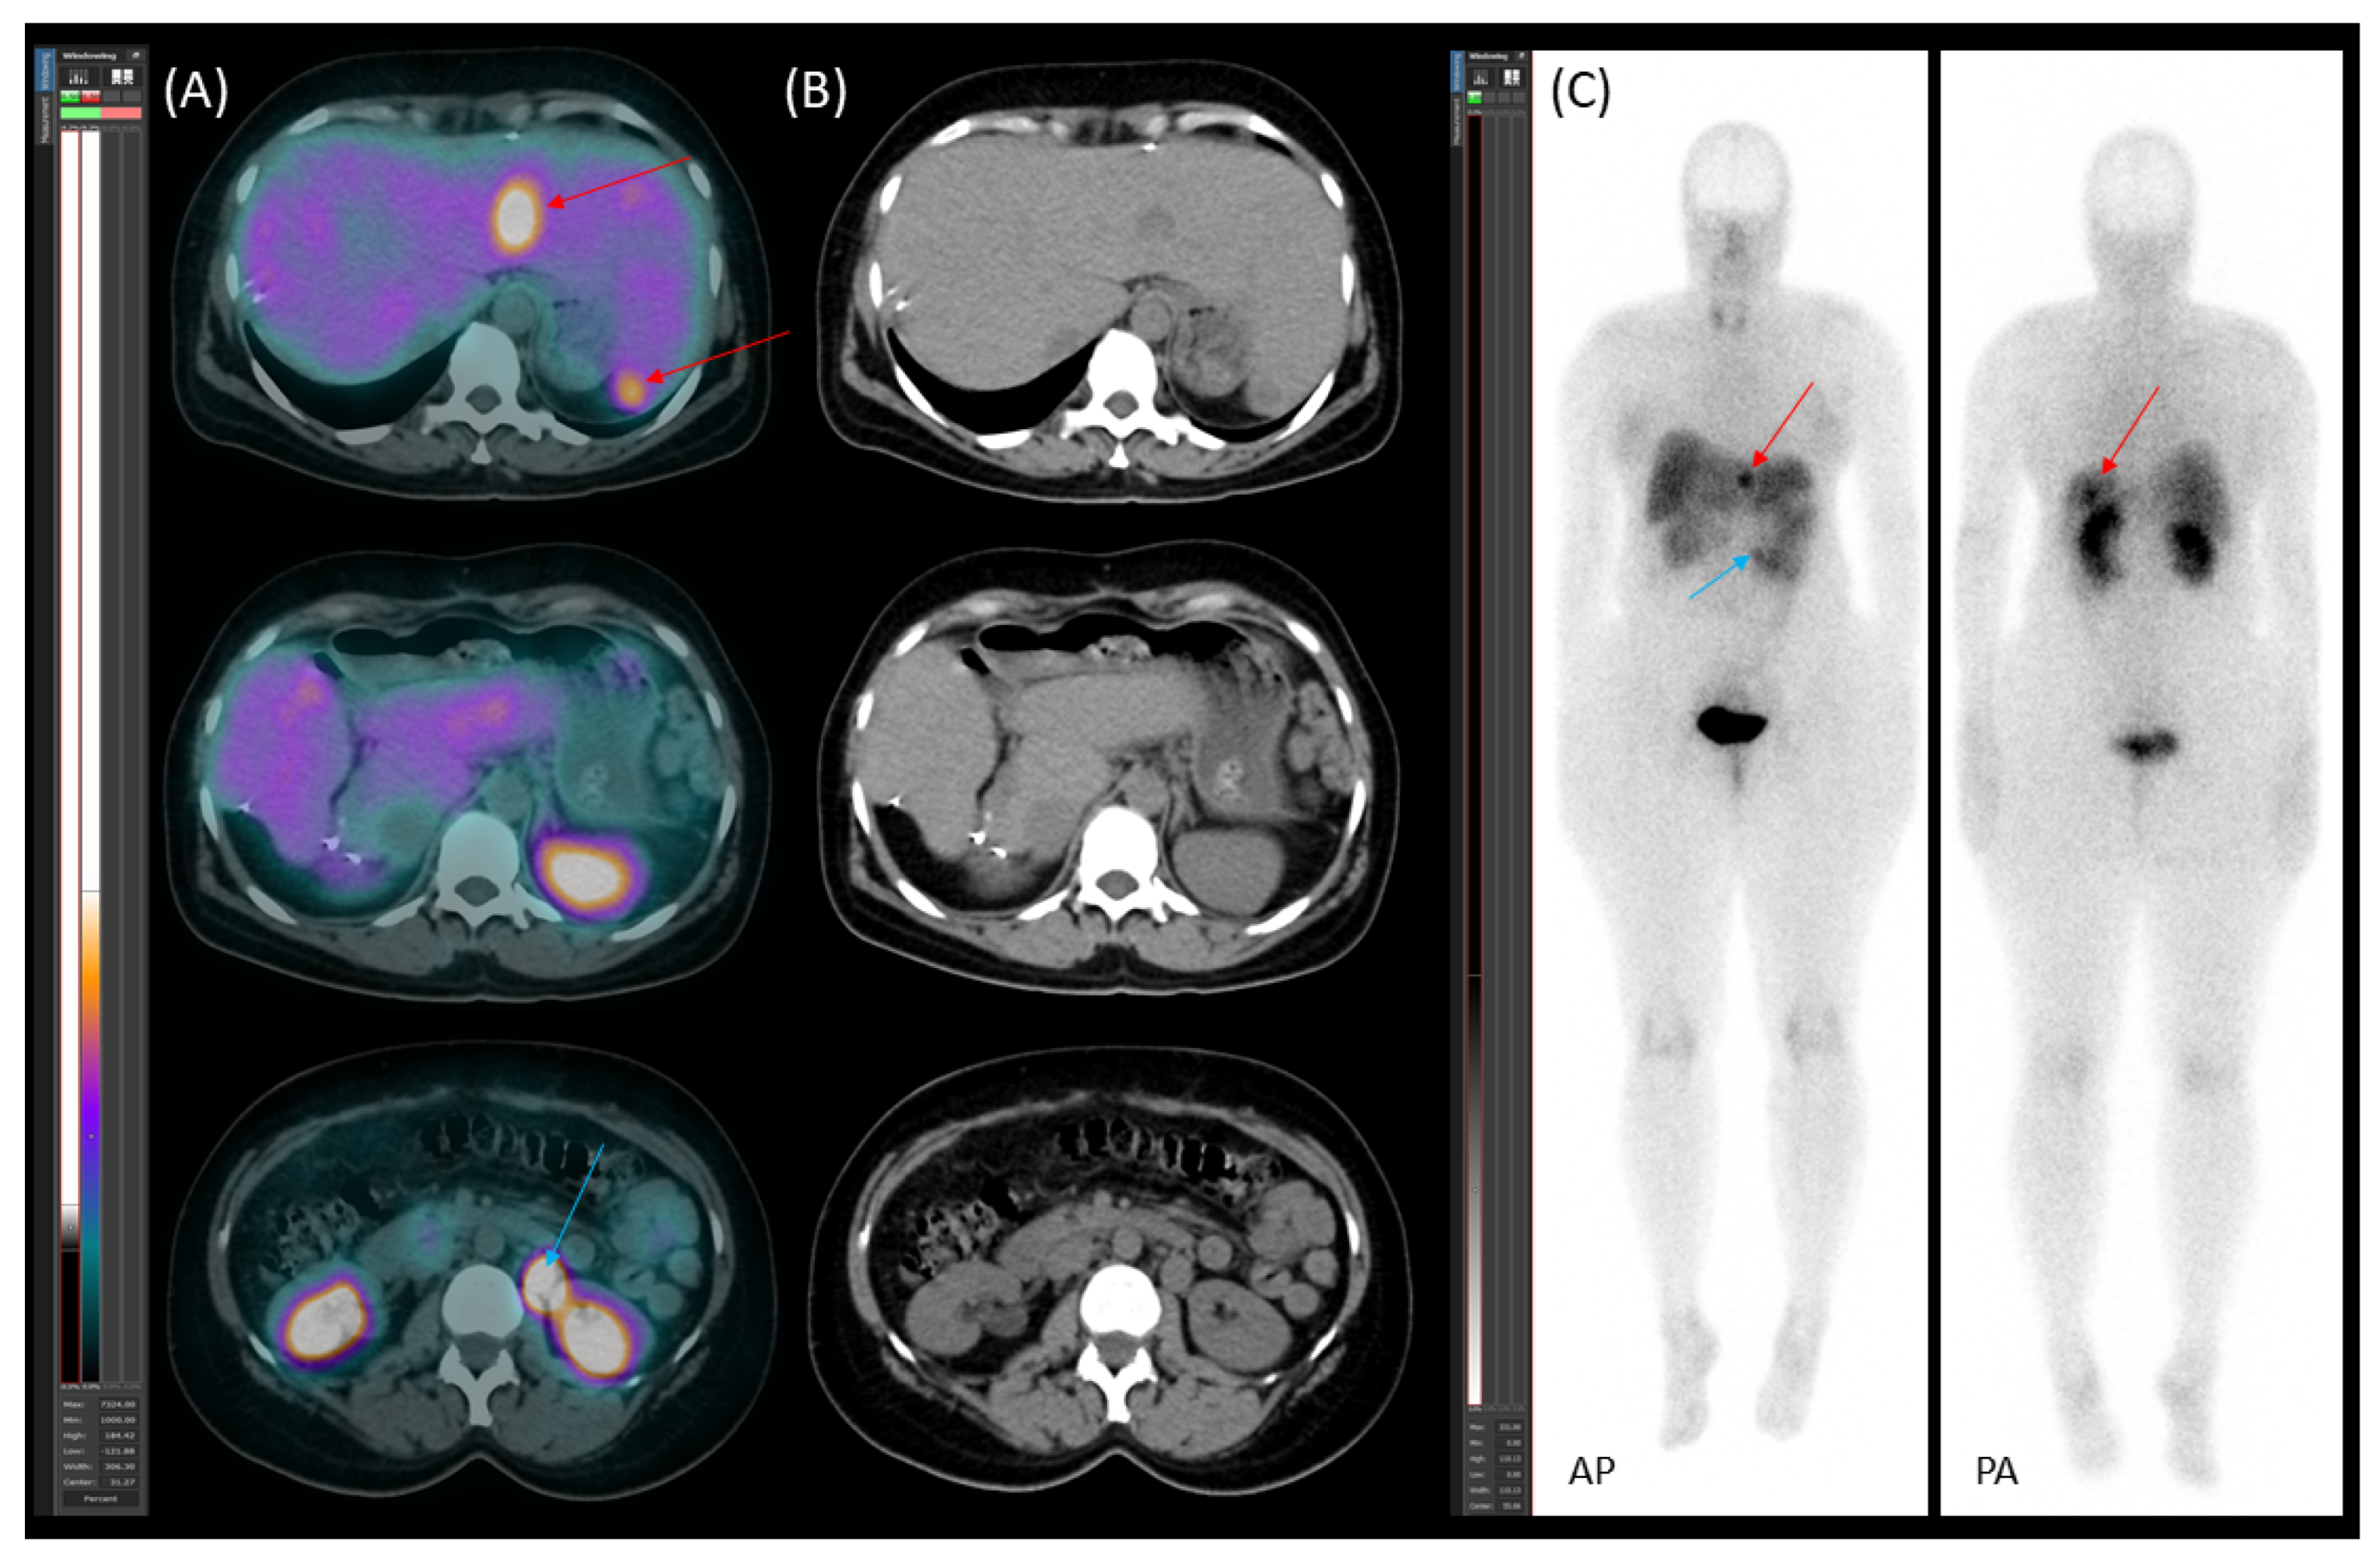

2.4. Follow-Up, Disease Progression, and Treatment